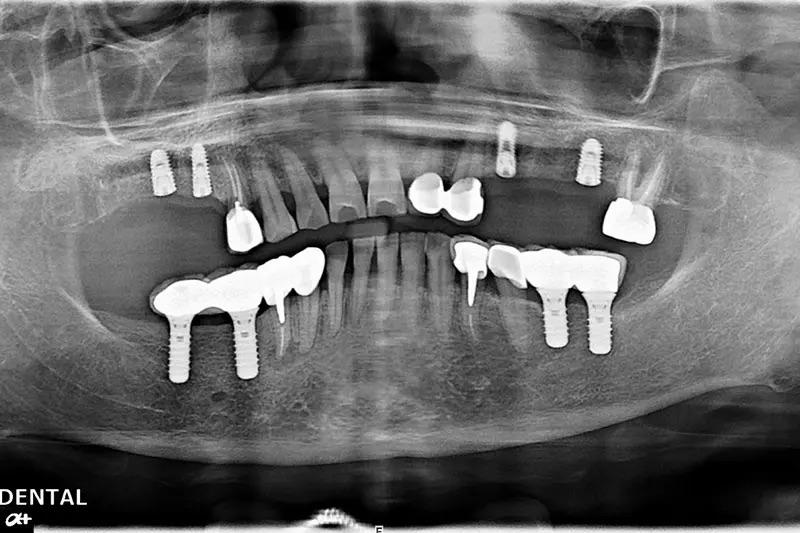

植牙成功案例